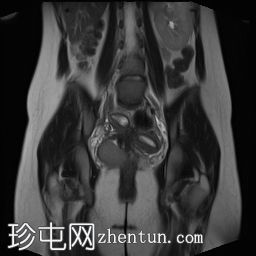

冠状位

T2 加速位

T2 TSE FS

T2

盆腔增强 MRI 检查增强了我们对 CT 扫描中发现的病变的理解。右肾发育不全,左肾肥大伴肾积水,双子宫完整,阴道隔膜,发育不全侧阴道积血。

双侧卵巢均有多个功能性囊肿,右侧卵巢可见黄体囊肿。

道格拉斯囊内可见少量游离液体。

左侧

泌尿

系统置入JJ支架,左侧输尿管下1/3扩张。

CT和MRI检查结果为Herlyn-Werner-Wunderlich综合征的典型表现,其特征为经典的三联征:III型苗勒氏管异常(完全性双子宫)、中肾管异常(肾发育不全)以及肾发育不全侧阴道积血。